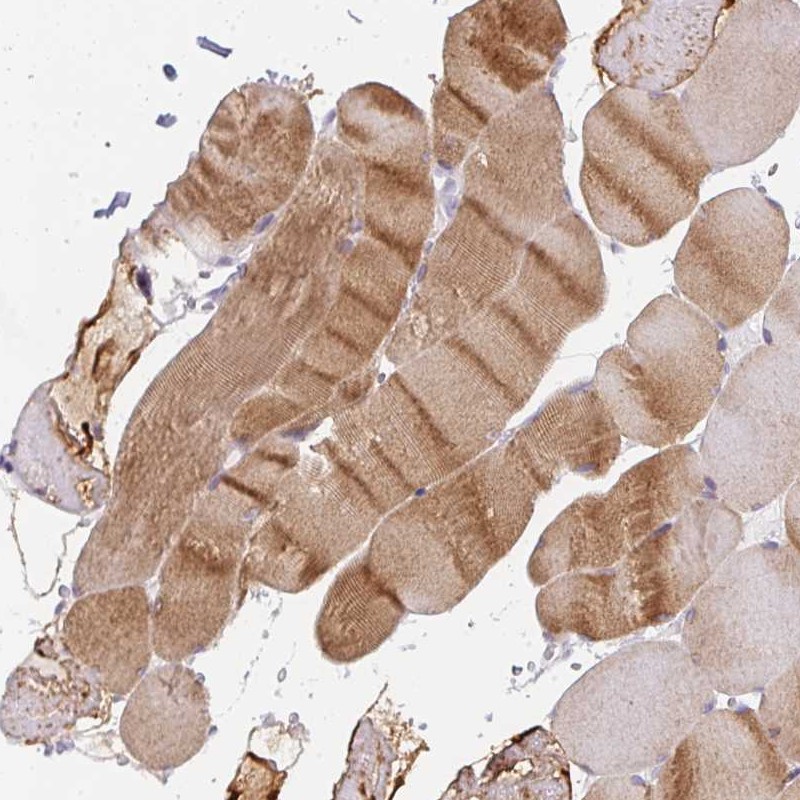

Immunohistochemistry analysis in human skeletal muscle and heart muscle tissues using Anti-CACNA1S antibody. Corresponding CACNA1S RNA-seq data are presented for the same tissues.